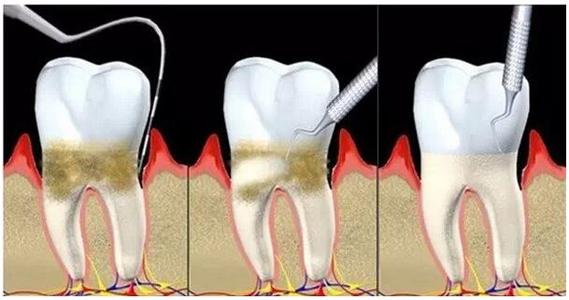

本病患者一般年齡較小,發病可開始於青春期前後。本病一個突出的表現是局限型患者的菌斑、牙石量很少,牙齦表面的炎症輕微,但卻已有深牙周袋,牙周組織破壞程度與局部刺激物的量不成比例。牙齦表面雖然無明顯炎症,實際上在深袋部位是有齦下菌斑的,而且袋壁也有炎症,且探診後有出血。廣泛型的菌斑牙石量因人而異,多數患者有大量的菌斑和牙石,也可很少;牙齦有明顯的炎症,呈鮮紅色,並可伴有齦緣區肉芽性增殖,易出血,可有溢膿,晚期還可以發生牙周膿腫。

本病還常有家族聚集性。病變常導致患者早年失牙,因此,特別強調早期、徹底的治療,主要是徹底消除感染。